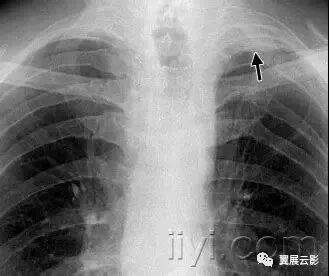

六、顶冠或肺尖帽

病理:是肺尖的帽状病变,常由肺内或者胸膜的纤维化,向下牵拉胸膜外脂肪,也可能是慢性缺血导致脏层胸膜的透明斑形成所致。随年龄增长,发病率增加。主动脉撕裂导致的血肿,或者炎症或者肿瘤,导致液体积聚在胸膜腔或者壁层胸膜外,也可以出现此征象。

平片和CT:常见表现是均匀的软组织密度,位于单侧或者双侧肺尖之上呈帽状,下界尖锐且不规则。厚度可变,甚至可达30mm。有时候在横断CT上,肺尖帽可以类似肺尖的实变。